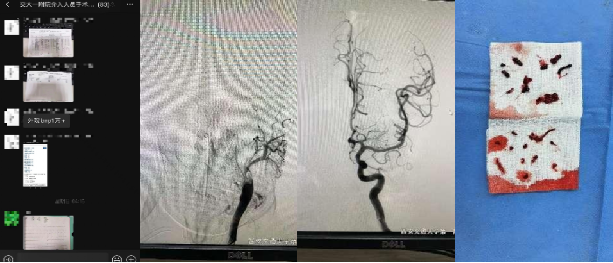

随着绿色通道的铃声响起,40岁的年轻患者突发左侧肢体无力、反应迟钝,120急救车到达时,卒中中心神经内科脑血管团队已经在急诊科待命,迅速启动评估和急救,在急诊科、影像科、介入手术室的通力配合下,成功实现脑血管开通,患者的肢体和意识恢复如常。

凌晨4点,人们还在熟睡之时,又一例57岁患者被发现失语伴右侧肢体活动障碍,伴有近期心梗、胸腔大量积液、可疑肿瘤等复杂病情,每一项都是对开通手术的巨大挑战,如果放弃必然意味着无法挽回的悲惨结局,卒中中心神经内科脑血管团队迎难而上,成功取出了大量栓子,继而在重症团队和心内、胸外、超声等兄弟科室的通力配合下,患者的脑心功能逐渐稳定,已经能够配合自主活动。只要电话铃声响起,卒中中心绿色通道就会立即启动,一例又一例的患者在这里得到成功救治。在这个合家团圆、平安祥和的假期里,是他们用行动践行着“健康所系、性命相托”的誓言,守护着脑卒中患者的大脑生命线。

82岁的老人,反复发生的脑梗,迂曲的通路,脆弱的血管,反复挑战着患者的安危,卒中中心介入团队细致耐心,稳步处理,最终成功开通了血管,避免了高灌注综合征的发生,老人术后激动的举起双臂,为医护们点赞。